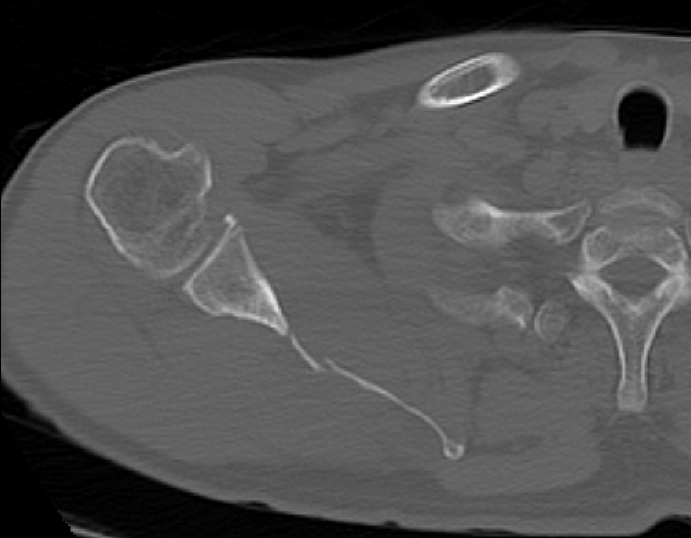

- M/50대

- fall down

- X-Ray 검사 상 견갑골 골절의심 됨

- Axial Scan 후 MPR로 Axial, Coronal, Sagittal image Recon 함

mildly displaced fracture of body of scapula.